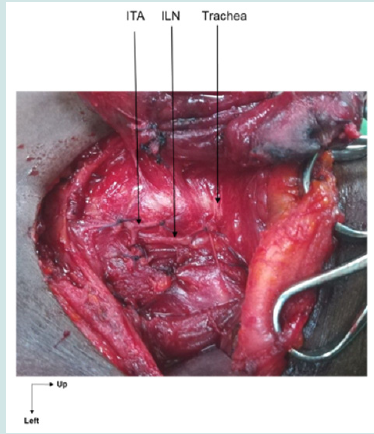

The recurrent nerve retro-crossed the ITA branches in 70.8% of cases on the right and 78.57% on the left, pre-crossed them in 20.8% of cases on the right and 14.29% on the left and passed between them in 8.3% of cases on the right and 7.14% on the left (Figures 1,2 and 3).

The ILN was attached to the posterior surface of the right thyroid lobe in 10 cases (41.7% of 24 right lobes), with no change in its course. It was attached to that of the left thyroid lobe in 11 cases (38% of 29 left lobes), with a modification of its course in 2 cases (Figure 4).

The inferior laryngeal artery was identified on the right in 21 cases, or 87.5% (N=24), and on the left in 26 cases, or 89.7% (N=29). In all these cases, it accompanied the recurrent nerve until it entered the cricotracheal angle (Figures 5,6 and 7).